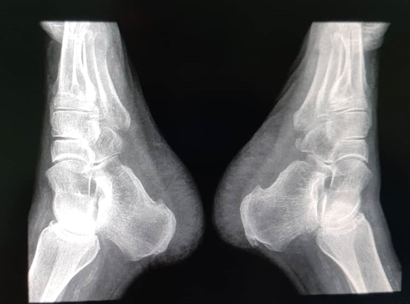

The image studies performed in a serial way, allow to observe the osteolytic process and the inflammatory response seen in those chronic cases. MRI, is especially useful in evaluating soft tissues, and the computed tomography, very much useful in evaluating bone destruction, worked together in these cases. It should be advice, the use of the bone scan, or PET-CT or virtual-PET, to discard polyarticular affectation. This entity is very often confused with other pathologies. Differential diagnosis has to be made with osteomyelitis, Paget’s disease, sarcomas and other pseudo tumoral lesions, which usually are the initial diagnosis, and TBC is a discard diagnosis. The adequate diagnosis is made late because of lack of pathognomonic findings (Figure 1 - 4).10

Figure 2 Both calcaneus x-ray in lateral 10-26-2019.